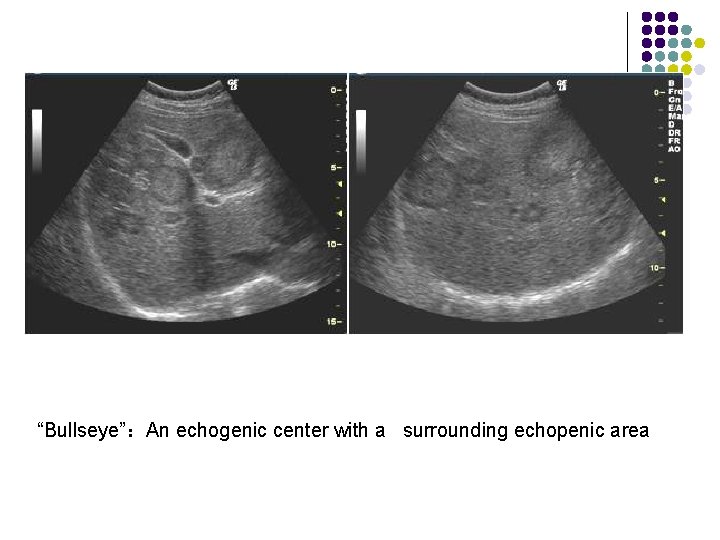

Metastases to liver l l l Organ of origin: colon(42%); stomach(23%); pancreas(21%); breast(14%); lung(13%) Number : multiple(98%); solitary(2%) “Bullseye”:An echogenic center with a surrounding echopenic area Echopenic : Less echogenic than the surrounding liver Echogenic More echogenic than the surrounding liver

“Bullseye”:An echogenic center with a surrounding echopenic area “牛眼征”

“Bullseye”:An echogenic center with a surrounding echopenic area